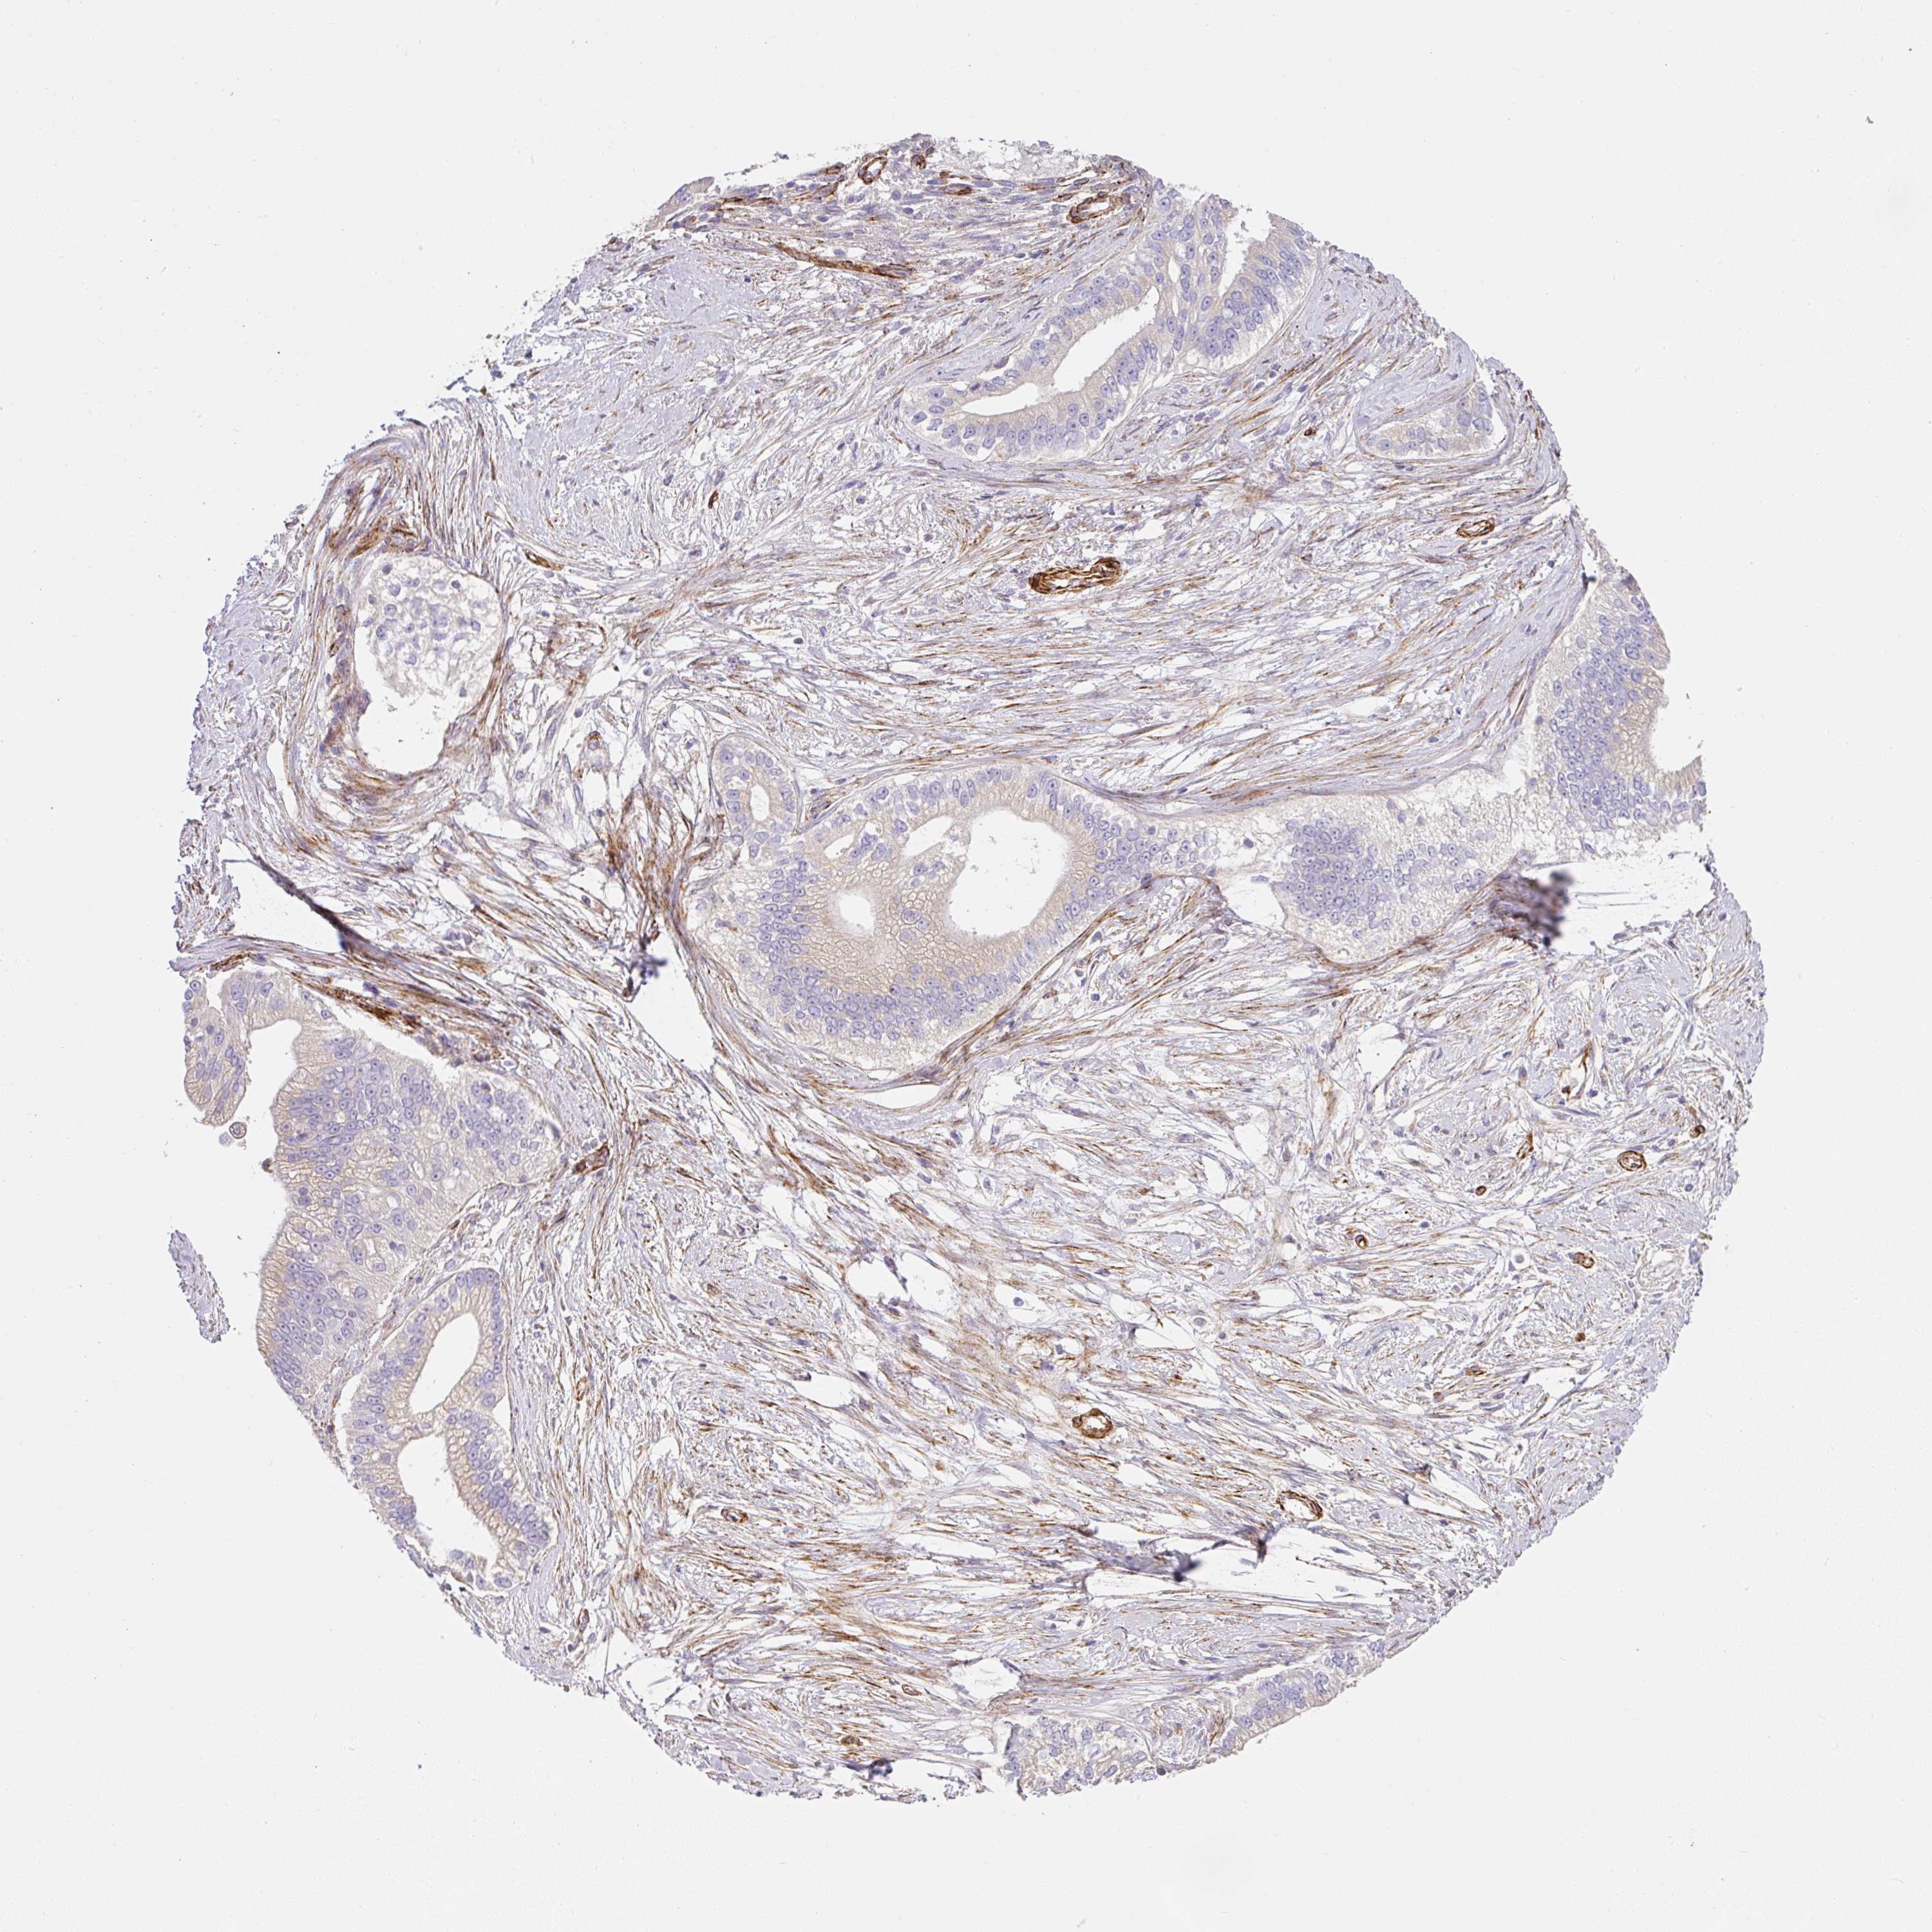

PANCREATIC CANCER - Protein expressioni

A mouse-over function shows sample information and annotation data. Click on an image to view it in a full screen mode. Samples can be filtered based on level of antibody staining by selecting one or several of the following categories: high, medium, low and not detected. The assay and annotation is described here.

Note that samples used for immunohistochemistry by the Human Protein Atlas do not correspond to samples in the TCGA dataset.

Antibody stainingi

Antibody staining in the annotated cell types in the current human tissue is reported as not detected, low, medium, or high, based on conventional immunohistochemistry profiling in selected tissues. This score is based on the combination of the staining intensity and fraction of stained cells.

Each image is clickable and will lead to virtual microscopy that enables deeper exploration of all samples and also displays staining intensity scores, fraction scores and subcellular localization as well as patient and tissue information for each sample.

Antibody HPA052708

Staining

Adenocarcinoma, NOS